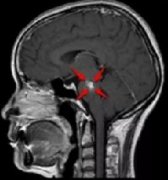

脑部磁共振成像(MRI)显示一个大的混合微小不均匀增强的囊实性脑室内肿块,伴有内部钙化和病灶周围脑水肿,主要位于左侧侧脑室的左三角区和体部,导致中度脑积水、低钙血症和左侧...

鞍内脑海绵状血管瘤案例,颅内出血在磁共振成像(MRI)上具有特征性表现,包括T1加权像上的等强度、T2加权像上的高强度和鞍区钆增强T1加权像上的弥散均匀强化。在这篇报告中,我们提...